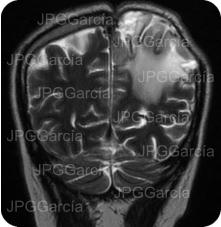

Resonancia magnética de cráneo en secuencias T1 y T2 que muestran una lesión ocupante de espacio de localización fronto temporal izquierda que ejerce efecto de masa aunado a edema perilesional